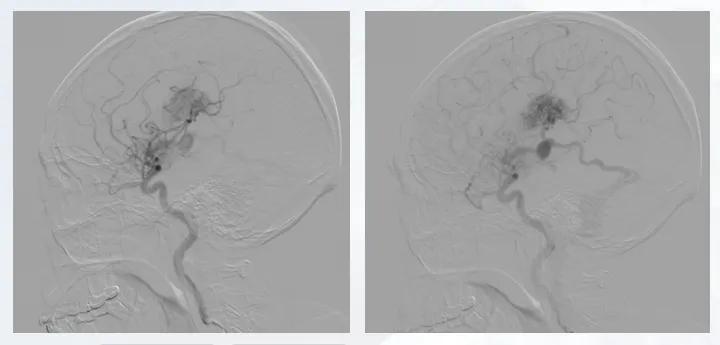

患者因突发意识不清、肢体抽搐2 h入院,中度昏迷状态,气管插管,双侧病理征阳性,头颅CT提示顶枕叶大量出血并破入脑室。入院后开通绿色通道,行急诊脑室外引流降低颅内压。血管造影提示病变由大脑后动脉多支供血,存在皮层静脉向矢状窦引流及深静脉引流,可见明显静脉湖。

图2 患者血管造影图